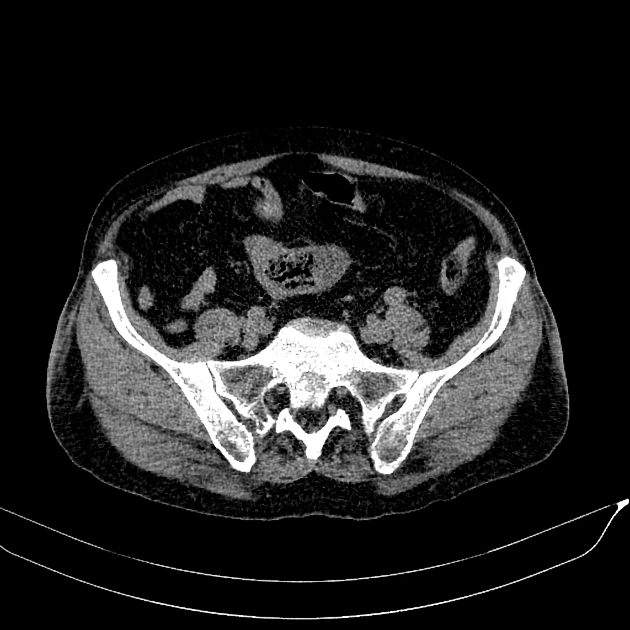

Bezoars

» Thông tin: Nam giới – 80 tuổi.

» Lâm sàng: Đau bụng / Nôn.

# Tắc ruột non do bã thức ăn.